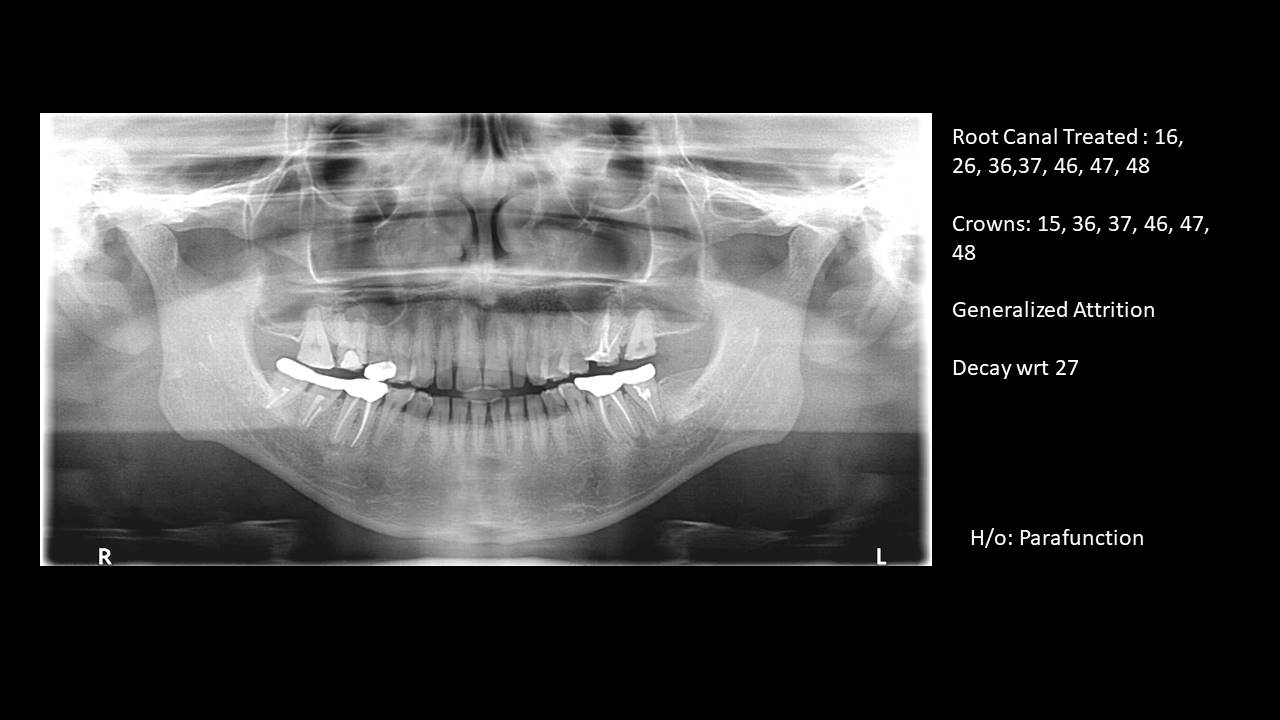

Full Mouth Rehabilitation (FMR) is one of the most comprehensive and transformative treatments in modern restorative dentistry. For patients suffering from severe wear, missing teeth, chronic jaw pain, or collapse of facial height, FMR offers a complete functional and aesthetic revival.

Full Mouth Rehabilitation (also called full mouth reconstruction) is the systematic rebuilding of the entire dentition. It addresses:

- Severe tooth wear (attrition/erosion)

- Endodontic stabilisation

- Worn, flattened, or eroded teeth

- Bruxism damage